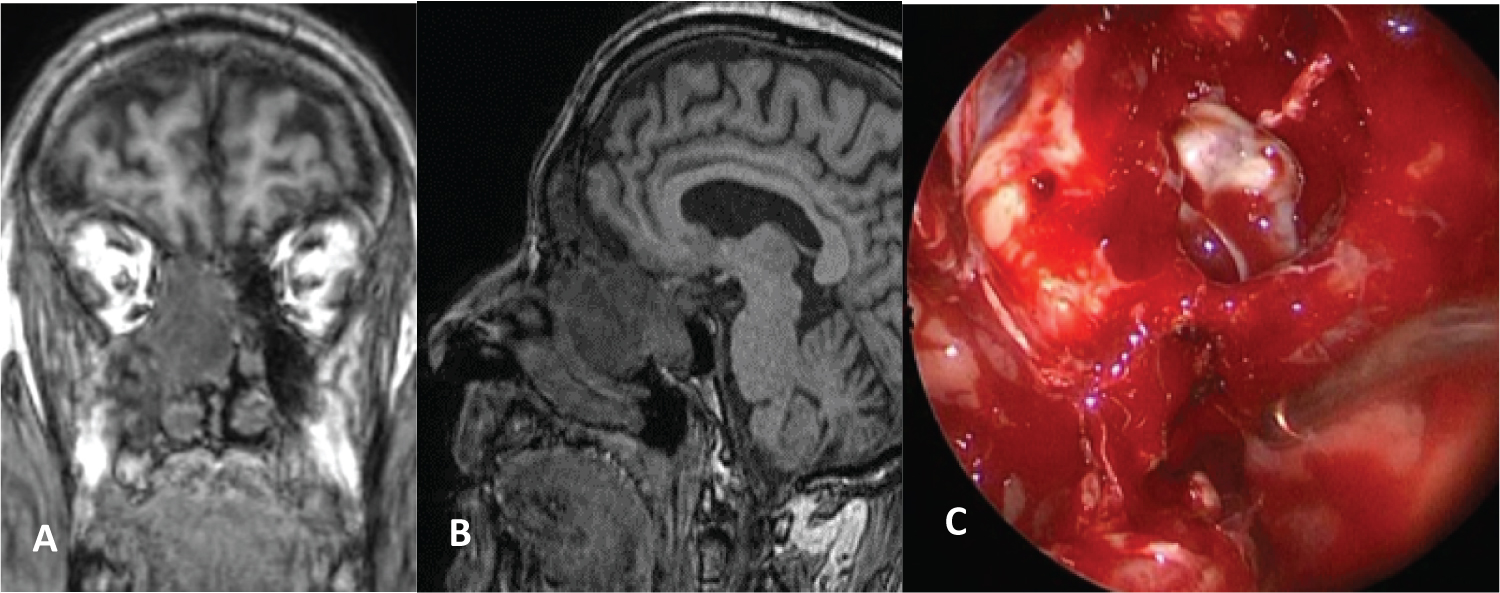

After year 2000, the endonasal approach was used with 0° and 30° endoscopes. Tumors that were located in the nasal cavity and in the ethmoid were resected through this approach (Figure 3) and in another patient who had a schwannoma located in the maxillary sinus and pterygomaxillary fossa, a wide middle maxillary antrostomy with resection of the posterior wall of the maxillary sinus and an approach to the pterygomaxillary fossa was performed to resect the tumor (Figure 4).

Figure 3: Ethmoidal Schwannoma. A) Coronal and sagittal MRI; B) Endoscopic resection; C) Maxillary antrostomy, anterior and posterior ethmoidectomy, sphenoidotomy and dissection of the tumor from the the skull base. View Figure 3

The ethmoid is the most common site of rhinosinusal location, followed by the maxillary sinus, the nasal cavity, and the sphenoid [5].